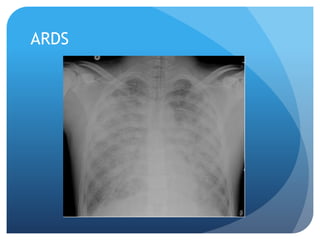

Acute Resp Distress Syndrome

(ARDS)

 Pt background:

 Severe multiple trauma

 Aspiration of gastric contents

 SEPSIS

 Shock/ toxic inhalation/ near-DROWNING

SX: tachypnea. FROTHY PINK/ RED SPUTUM.

CXR: Think fluid. Inflammation. Alveolar collapse.

*air bronchograms, patchy bilateral infiltrates that spare the

costophrenic angles.*

Normal CXR

ARDS